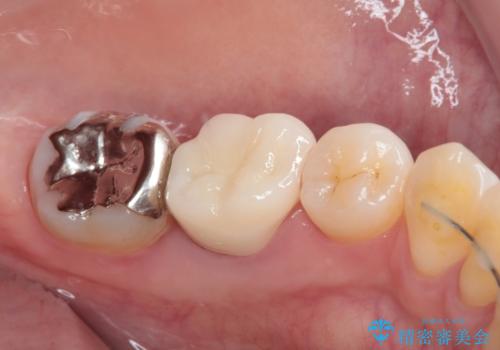

目立つ銀歯をオールセラミッククラウンで自然に|20代女性の審美補綴症例

- 矯正治療が終了し、歯並びが整ったことで左下の銀歯が目立つことを気にされてご来院されました。

「せっかく矯正できれいになったので、銀歯も自然な白い歯にしたい」というご希望でした。

患者様は根管治療のやり替えは希望されなかったため、ファイバーコア+オールセラミッククラウンによる補綴治療を行いました。